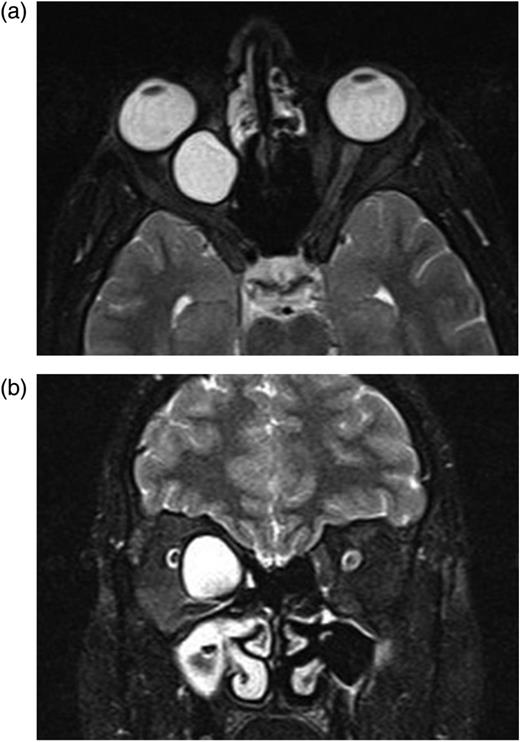

In the second postoperative month, the findings of ocular examination were the same. Control MRI revealed that there was a new small cyst in the intraconal space (Fig. 4a and b). Based on these findings, we planned the second operation via again medial transconjunctival orbitotomy. Peroperatively, we could not find remarkable cyst capsule. To prevent any inoculation, surgery area was washed with %0.9 hypertonic saline solution. Due to the postoperative edema, 80 mg systemic prednisolone was applied for 3 days. Systemic albendazole was applied twice a day for 2 months.

(a and b) After first operation, control MRI in the second postoperative month shows a small cyst displacing optic nerve laterally.